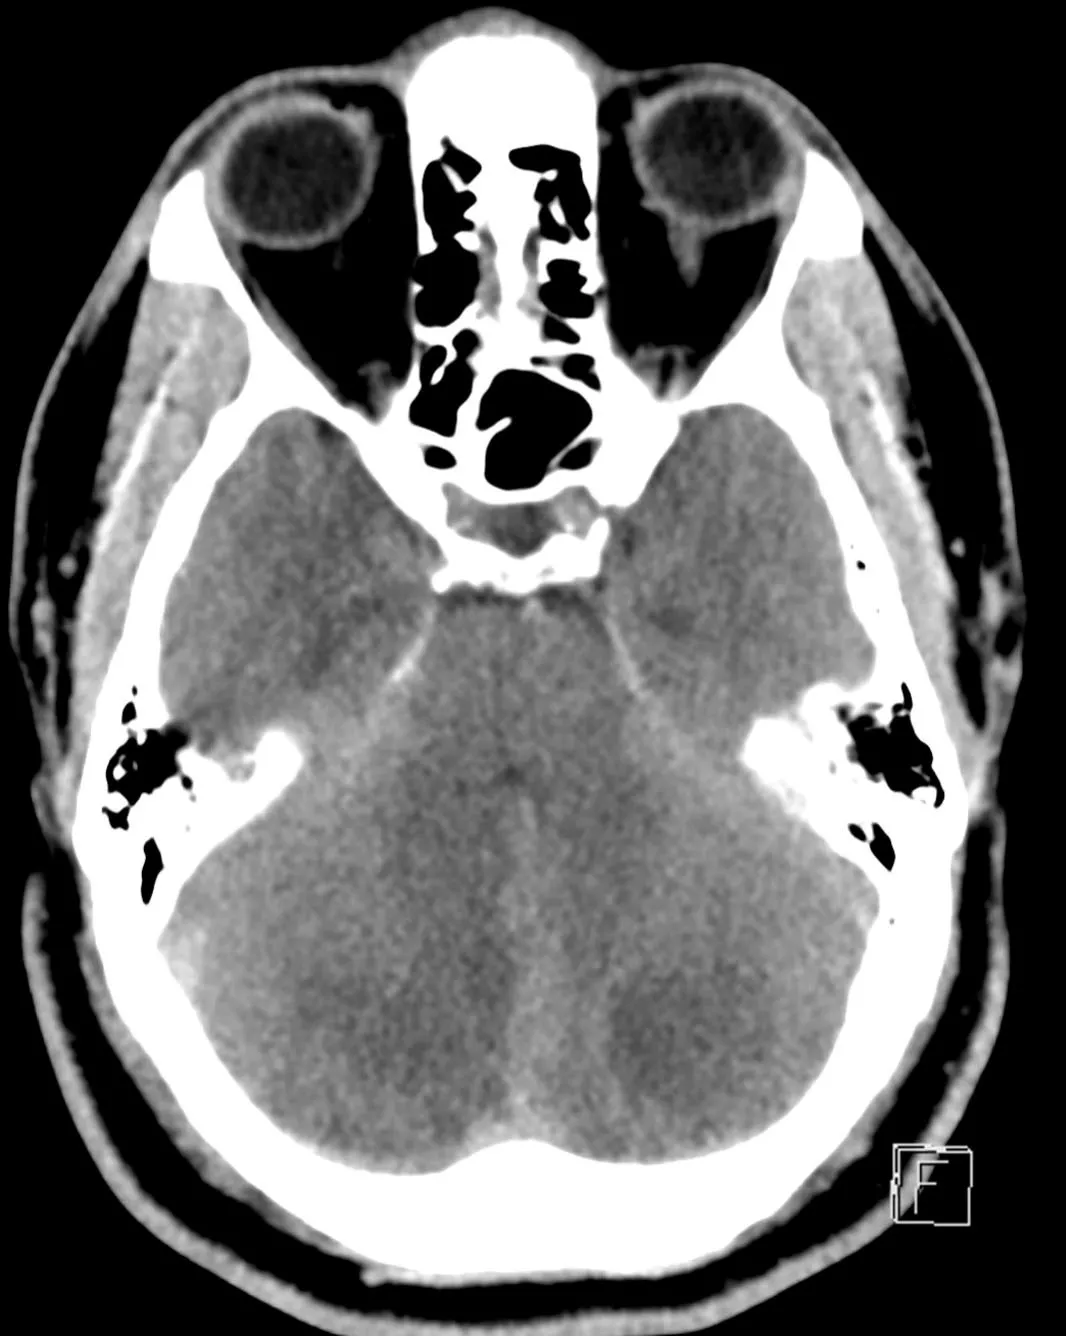

Approximately 12 hours after admission, the patient experienced a decline in his mental status, prompting a stat non-contrast computed tomography (CT) of the head which revealed bilateral cerebellar strokes. The associated cytotoxic edema resulted in significant mass effect on the 4th ventricle and early hydrocephalus.